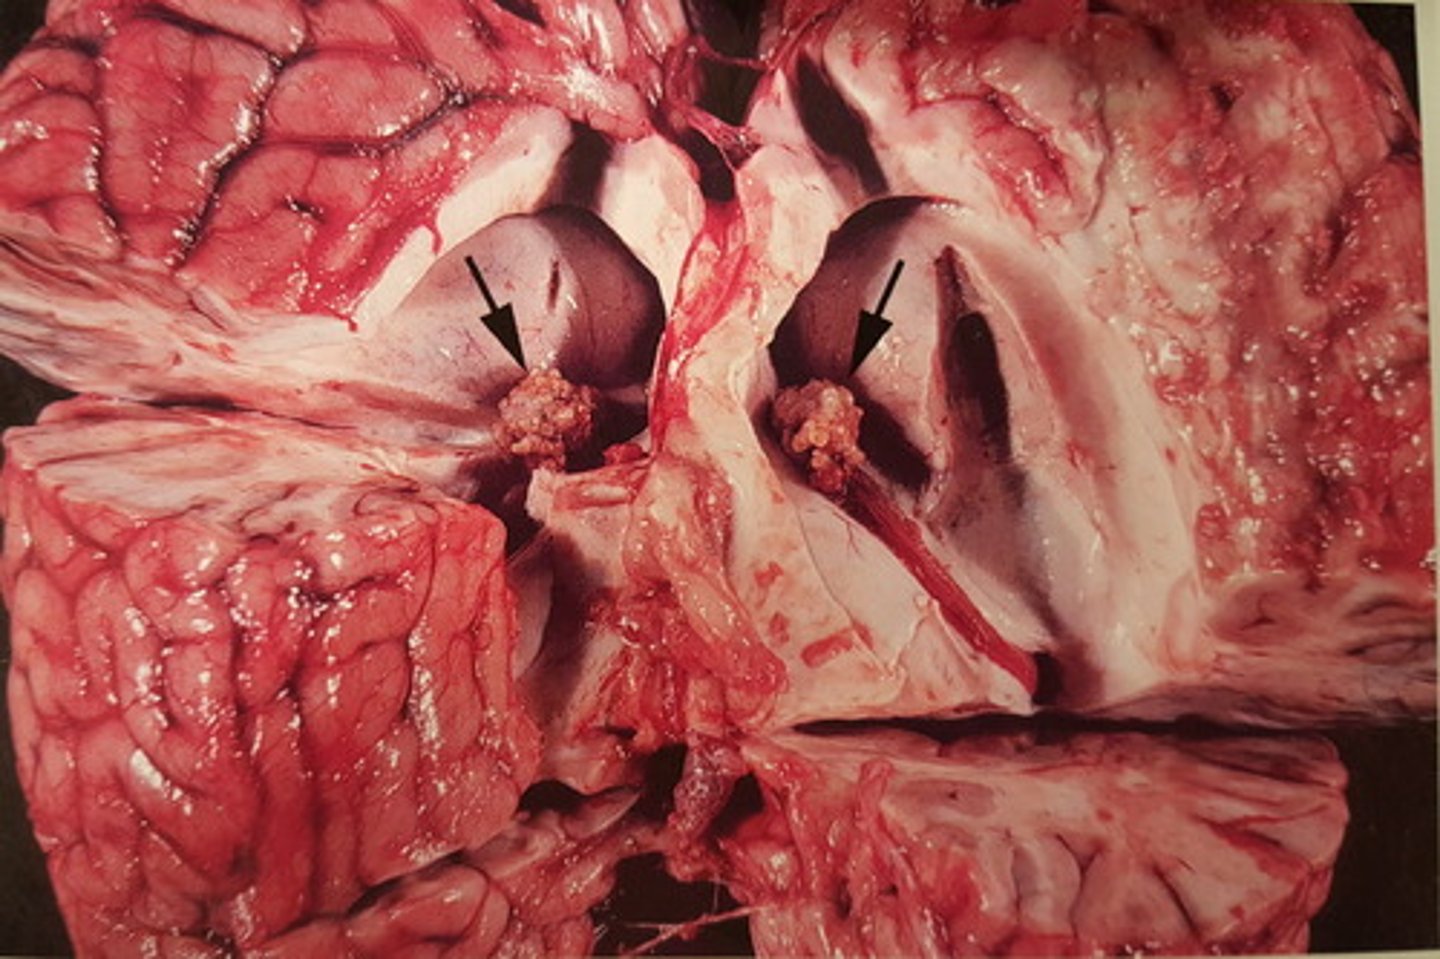

kronisk fibroniserende cholangioheptatitis (pile)

Ætiologi: Dicrocoelium dendriticum (den lille leverikte)

Lever fra får, hvad er den patoanatomiske diagnose og ætiologien?